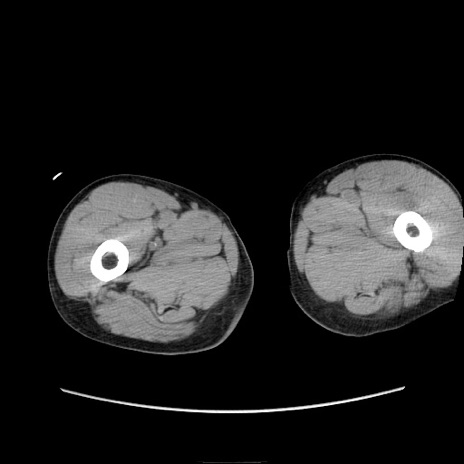

症例11(横断像)

【症例】 60歳代男性

【主訴】 下腹部痛

【現病歴】 本日夜中より下腹部痛の症状認め、受診。

【既往歴】 膀胱癌(膀胱全摘+尿管皮膚瘻術) 、胃癌術後

【身体所見】 BT 35.3℃、PR 58/min、BP 136/98mHg、腹部平坦、軟、腸蠕動音±、ストマ留置あり、左上腹部~正中部に圧痛あり、反跳痛なし。

【データ】WBC 5100、CRP0.01